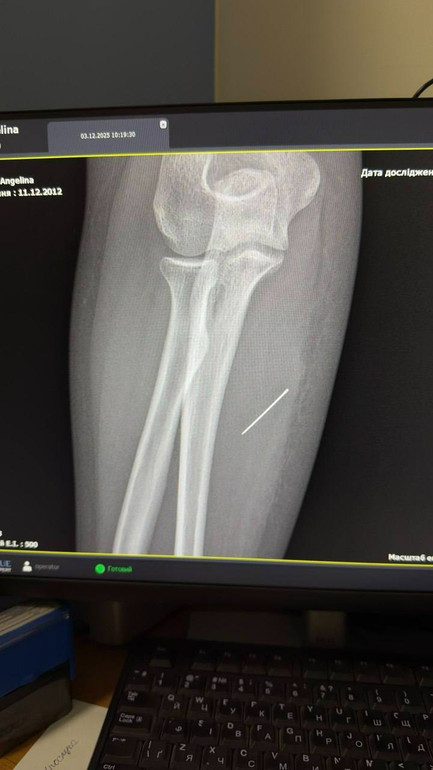

Голка не залишилася на місці, а протягом тижня просувалася глибше. Рентген допоміг лікарям побачити точну картину — голка застрягла глибоко в товщі м'яза під кутом 45 градусів.

Хірурги мали витягти голку рівно так само, як вона зайшла. Це критично важливо, бо якщо тягнути під іншим кутом, тонка голка могла зламатися. За допомогою ЕОП (електронно-оптичного перетворювача) визначили, де перебуває стороннє тіло, і через невеликий розріз та правильно і безпечно його вилучили.